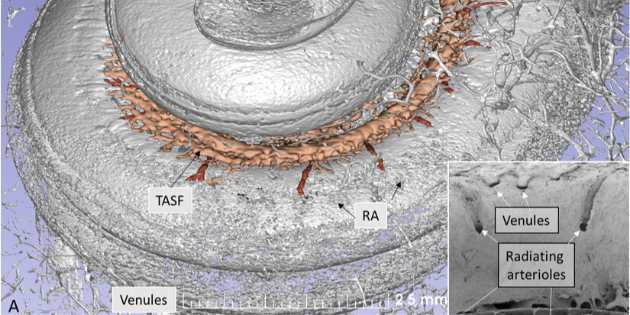

Des chercheurs suédois viennent de cartographier l'irrigation sanguine de la cochlée, située dans l'oreille interne,...